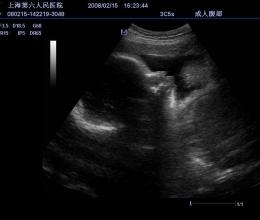

- Поддержка цветного, энергетического и импульсного допплеров для точной диагностики сосудистых патологий;

- Поддержка различных типов датчиков, включая линейные, конвексные и внутриполостные, что расширяет возможности диагностики;

- Режимы сканирования: B/M/Color Doppler/Color M/Power/Directional Power Doppler Flow Imaging;

- Программы расчетов и измерений для абдоминальных исследований (Abdomen/General Software Package);